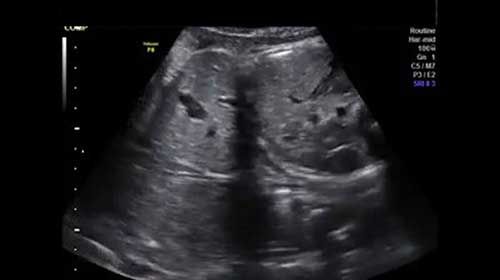

This image quiz focuses on the kidneys. Can you identify the abnormality seen in these ultrasound images of the fetal abdomen?

Challenge your diagnostic skills: What's going on with the kidneys in this fetus?